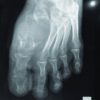

A 44-year-old previously healthy female presented reporting a slowly growing mass at the dorsum of her right midfoot (Fig. 1).

The patient was aware of the presence of the mass for many years; however, it became more symptomatic following a low energy sprain few months before consultation. Still, she was able to ambulate with no aids and wear normal shoes and had no need of analgesics. On clinical examination, the foot was neurovascularly intact with a normal range of motion and muscle power of all the regional joint and muscles, respectively. Skin color and temperature were normal. There was a semirigid palpable mass, relatively mobile over the dorsum of the first metatarsal, extending plantarly to the medial arch. Imaging studies on presentation included plain radiographs and an magnetic resonance imaging of the foot, which revealed a diffuse soft-tissue tumor encircling the first metatarsal and expanding beyond the borders of the regional foot compartments. The tumor had an intermediate to low irregular signal with no zones of necrosis or calcification (Fig. 2). The plantar distal metaphysis of the metatarsal showed an oval radiolucent zone with a concave configuration, whereas the cortex appeared intact (Fig. 3).